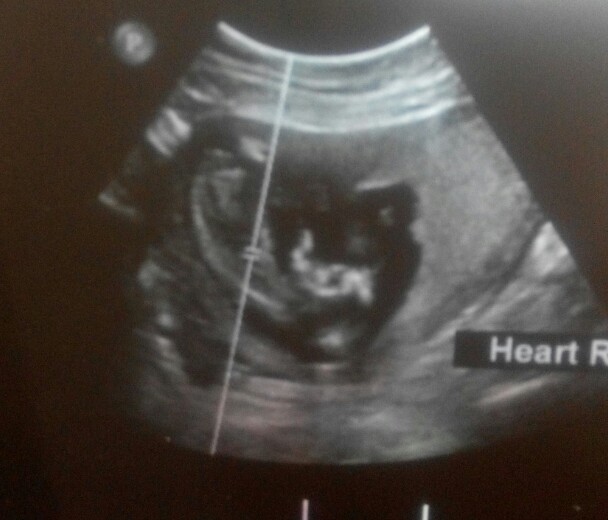

Experts, please see if the below ultrasound is good enough to let you guess if my daughter gets a brother or sister

Can't see an clues in this image. Any other pics?